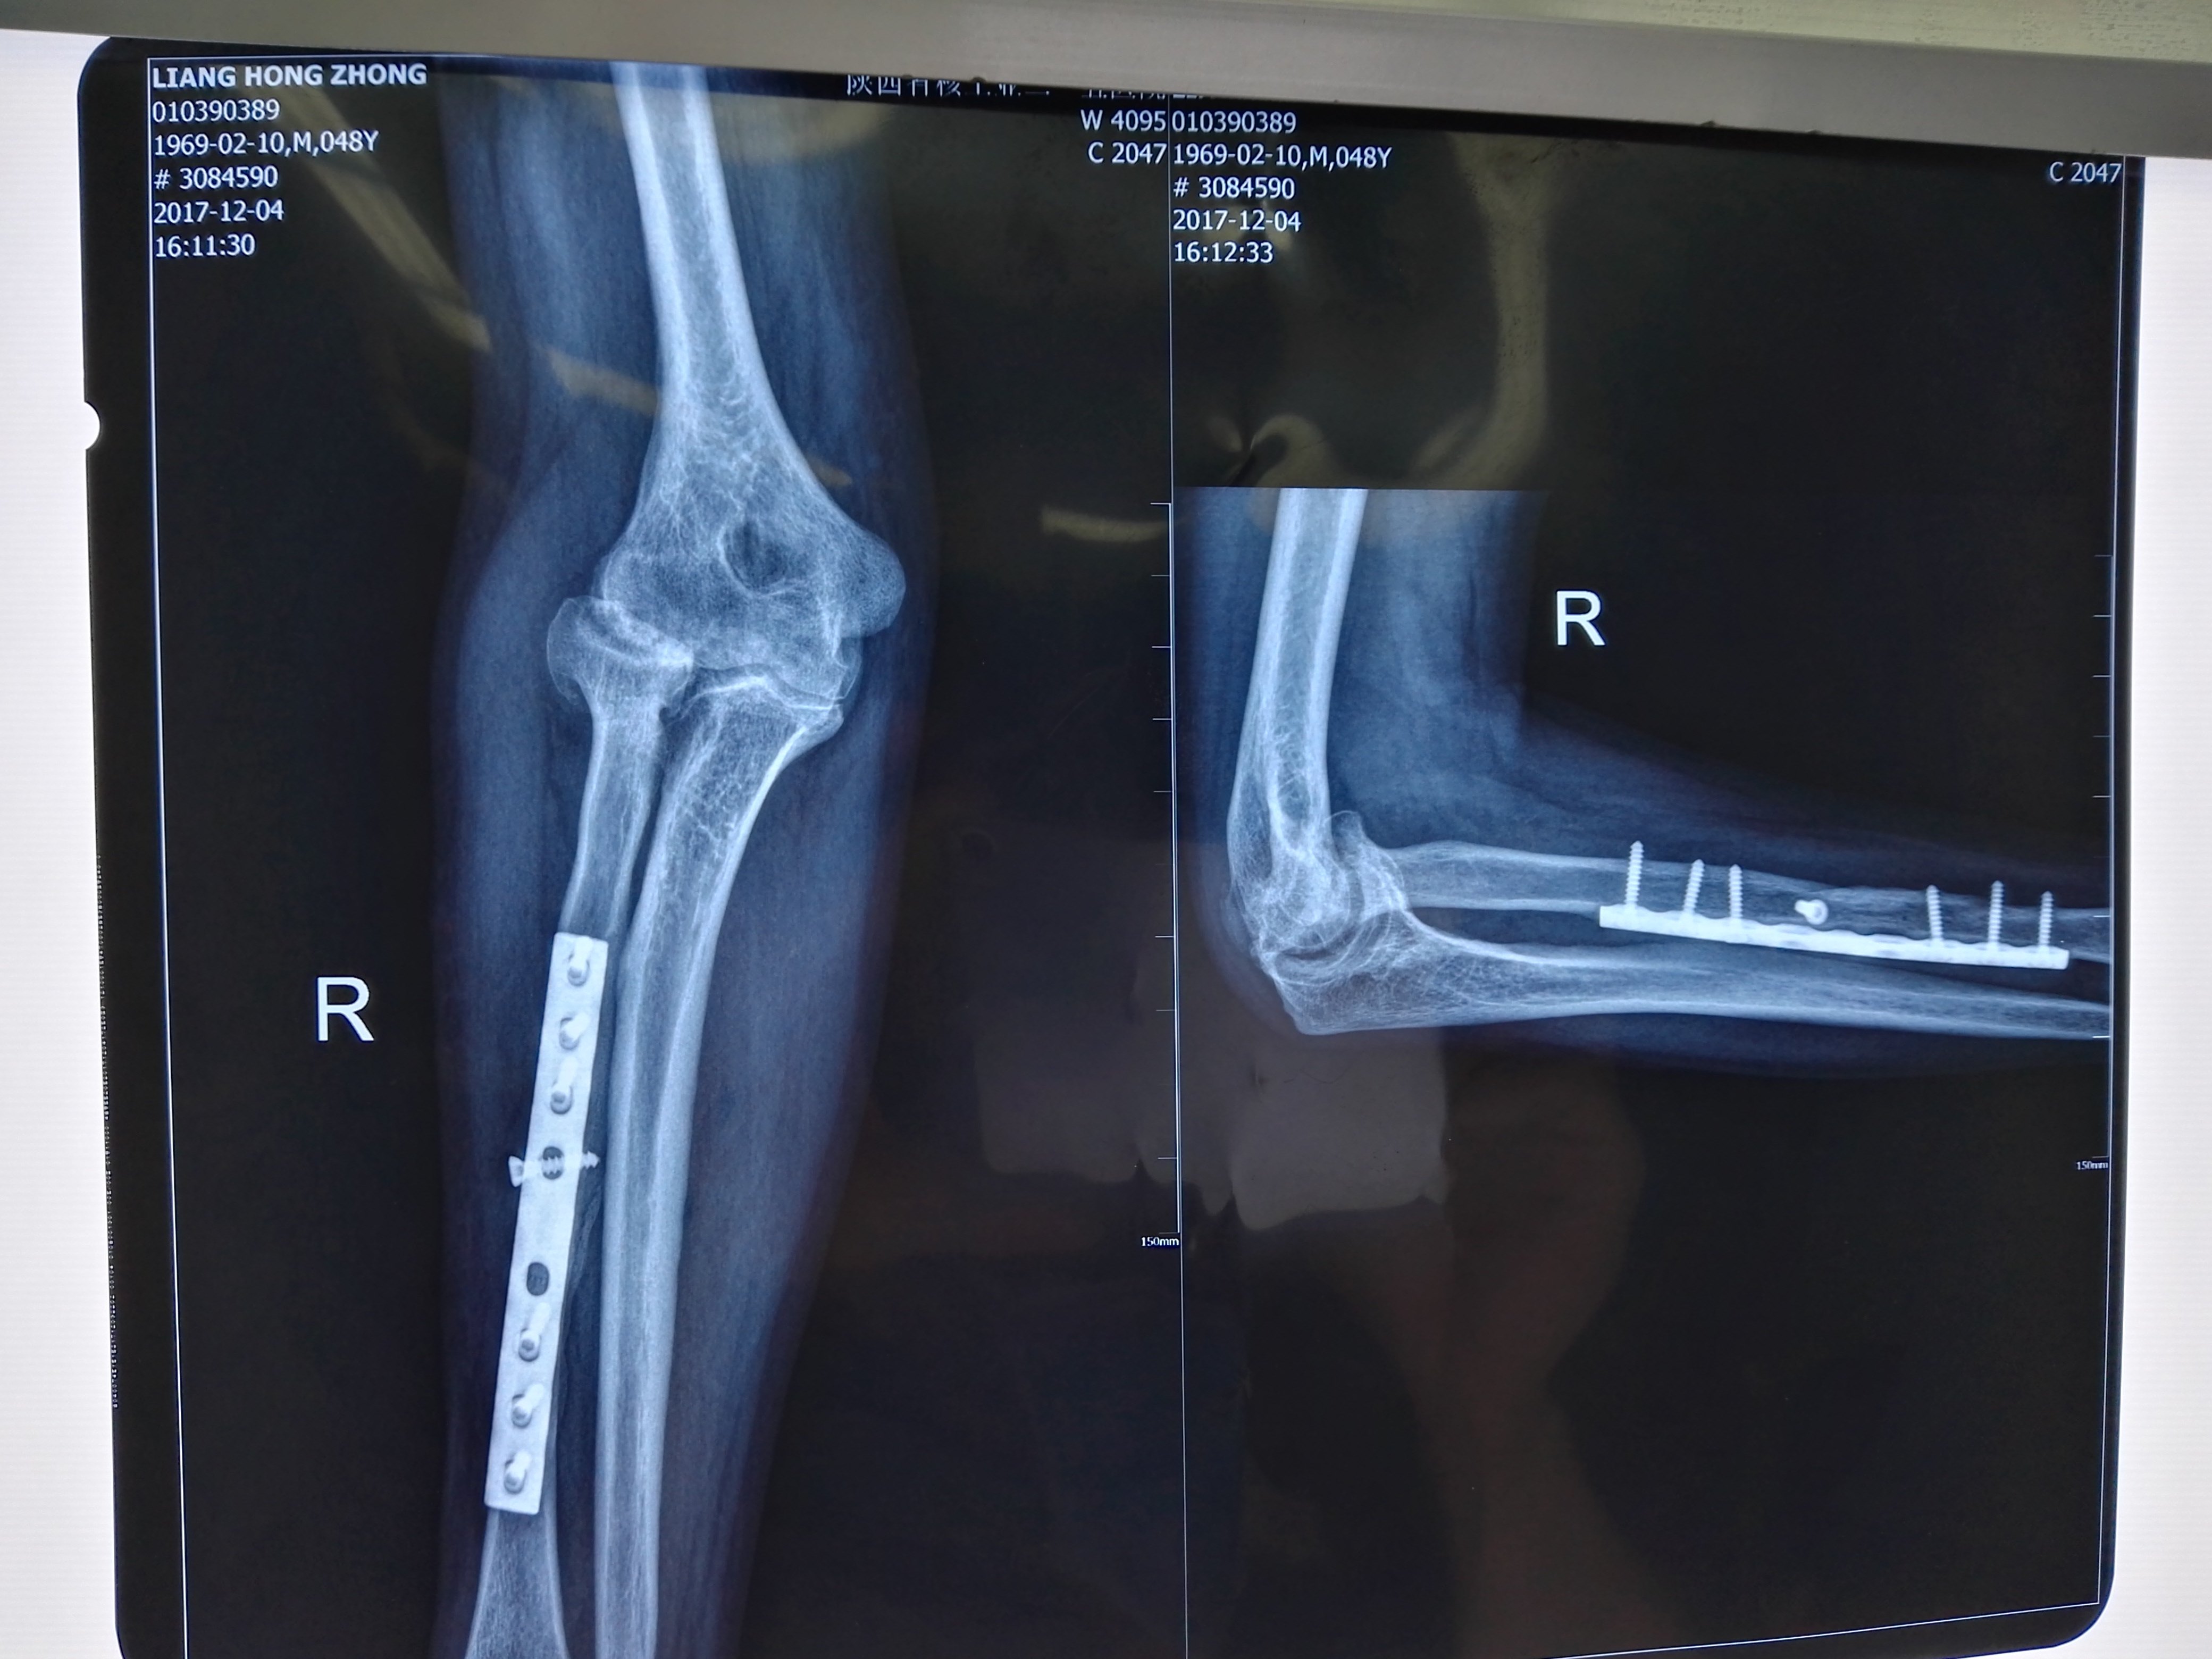

在杭州肘关节疼痛畸形多年治疗经历分享 知乎

肘部骨折手術後動作恐硬梆梆職能復健助恢復軟q不卡卡 亞洲大學附屬醫院